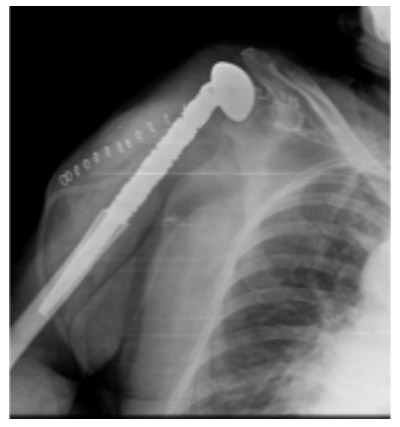

Post-surgery: A cemented proximal humerus tumor prosthesis implanted in the superior end of the right humerus is shown.